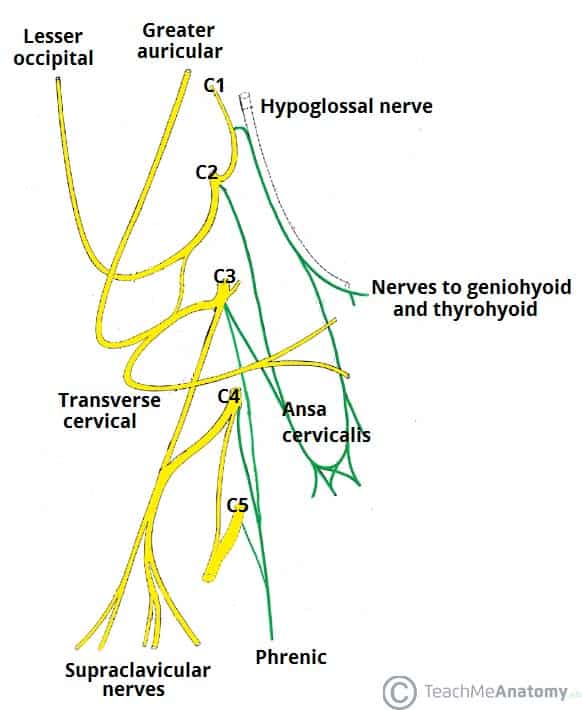

The Hypoglossal Nerve (CN XII) – Course – Motor – TeachMeAnatomy

The Phrenic Nerve – Anatomical Course – Functions – TeachMeAnatomy

The Tongue – Muscles – Innervation – Vasculature – TeachMeAnatomy